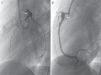

Asymptomatic intra-aneurysmal thrombosis was detected in one patient (case 3), initially by echocardiography and later by CCTA (Fig. 2) with origin in the right coronary artery (RCA), with a maximum diameter of 13mm, and in the ostial left anterior descending coronary artery (LAD). The patient received systemic thrombolytic therapy with r-TPA, infliximab, abciximab and IV heparin, and had mild systolic dysfunction. Magnetic resonance with IVPD confirmed that the thrombus was old due to the presence of necrosis in the septal and posterior regions and of collateral vessels in some areas. Treatment with ASA, acenocoumarol, angiotensin-converting enzyme inhibitors, carvedilol and spironolactone continued after discharge.

Another patient (case 1) received a diagnosis of intra-aneurysmal thrombosis in the RCA, with prescription of IV heparin sodium and r-TPA, and evidence of mild systolic dysfunction in the left ventricular ejection fraction (LVEF). Follow-up echocardiograms showed that the thrombus had dissolved and the LVEF had normalised, the follow-up CCTA confirmed the absence of intra-aneurysmal thrombotic lesions, and MRI with IVDP ruled out the presence of ischaemic or necrotic lesions and evinced the normalisation of LVEF. The treatment prescribed at discharge was prophylactic antithrombotic therapy and captopril as the sole therapy for myocardial function.

Patients made periodic follow-up visits on an outpatient basis that included electrocardiography, echocardiography every 3–6 months and CCTA every 12 months, and at least one myocardial perfusion scan (earlier cases) or a MRI scan with IVDP (Fig. 3) to assess function for the purposes of prognostication, which was repeated periodically in the 2 patients that had coronary thrombosis. A coronary angiogram was performed in the 3 earliest patients and in the 2 recent patients with intracoronary thrombosis after the initial phase of the disease (Fig. 4). The first 3 patients underwent ergometric stress testing, which they tolerated well, with normal findings in all.